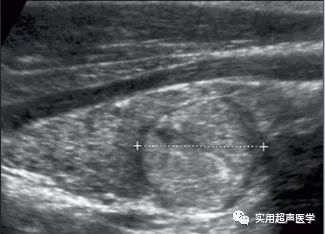

患者,男,40岁,患有弥漫性桥本甲状腺炎和结节性桥本甲状腺炎(FNA)。左侧叶显示高回声结节(光标)伴低回声晕。彩色多普勒显示结节为血管增生伴中央和外周血流。